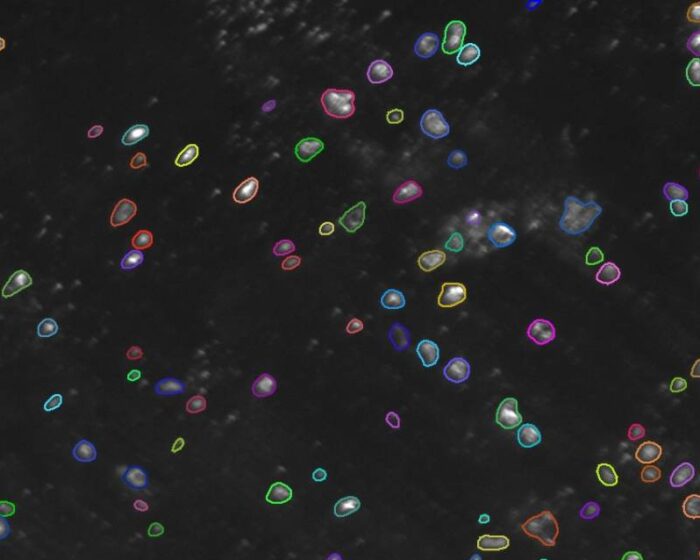

- Biomedical

- Cancer Research

- Cell Biology

- Histology/Pathology

- Life Science